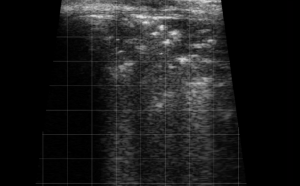

–Canine and Feline abdominal ultrasound videos were generously provided by the Cummings School of Veterinary Medicine at Tufts University.

–Equine distal limb ultrasound videos and bovine ultrasound videos were generously provided by the Virginia-Maryland College of Veterinary Medicine at Virginia Tech.

These videos are intellectual property and are provided for educational purposes ONLY. Usage of these videos for commercial and/or research purposes without permission is strictly prohibited.